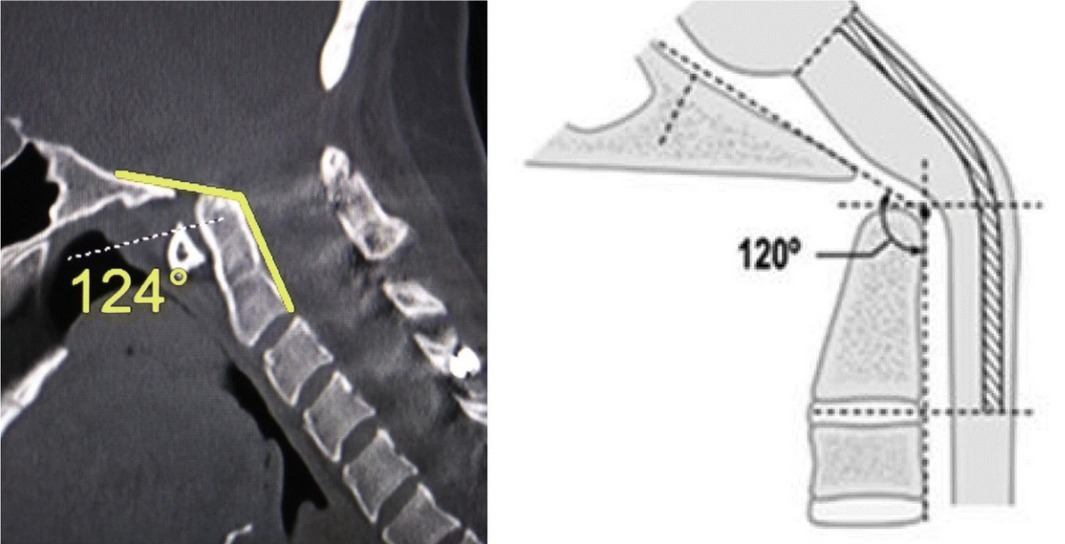

The clivo-axial angle (CXA) is a sagittal craniocervical measurement that quantifies the angular relationship between the clivus (posterior skull base) and the axis (C2). It reflects the degree of ventral kinking or kyphotic angulation of the cervicomedullary junction.

• Select a true mid-sagittal CT reconstruction that clearly shows the skull base, clivus, and C2 vertebral body.

• Draw the Clival Line:

• Trace a line along the posterior cortical margin of the clivus.

• Draw the Posterior Axial Line:

• Trace a line along the posterior cortex of the C2 vertebral body.

•  Extend both lines until they intersect.

• Measure the angle formed at the intersection of these two lines.

• This angle is the Clivo-Axial Angle (CXA), recorded in degrees.

• Normal: 135° - 165°

• Borderline: 125° - 134°

• Pathologic (ventral cervicomedullary compression): < 125°